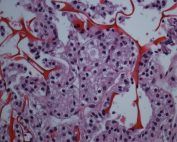

• Ematossilina-Eosina (EE)

Diversamente dai vetrini tradizionali o dalle tecniche a strato sottile, Cyto Matrix permette di mantenere intatta la disposizione spaziale delle cellule e dei micro-aggregati, offrendo una visualizzazione tridimensionale impossibile con le metodiche citologiche convenzionali.

Ne deriva un enorme vantaggio diagnostico: pur utilizzando un comune ago sottile, quindi una procedura minimamente invasiva, è possibile ottenere un risultato simile a una valutazione microistologica. Questo consente di migliorare in modo significativo l’accuratezza diagnostica, riducendo il rischio di referti inconcludenti e permettendo una migliore caratterizzazione del nodulo tiroideo.

Questa procedura non corrisponde alla classica tecnica del cell-block, poiché l’inclusione preventiva nella matrice mantiene intatti i dettagli citomorfologici e la disposizione originaria delle cellule.

• colorazioni di routine EE